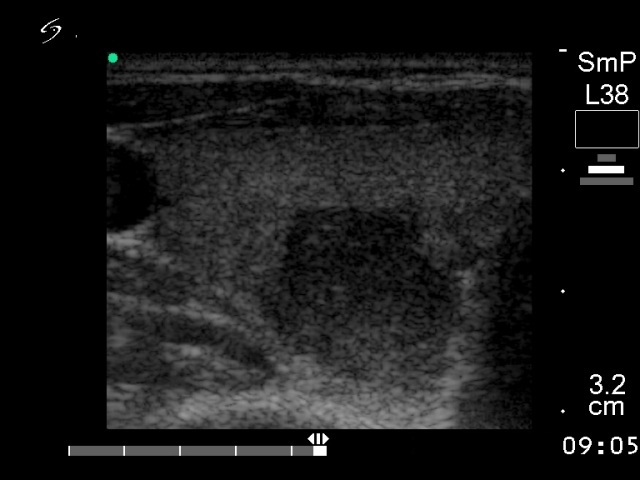

Follicular carcinoma - Case 9